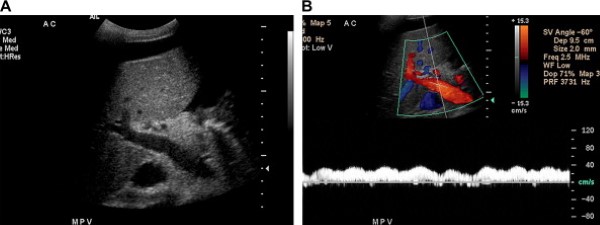

Tĩnh mạch cửa được tạo thành do hợp nhất tĩnh mạch lách với tĩnh mạch mạc treo tràng trên và mang máu từ ruột, tụy, lách tới gan (Hình 1). Các ngành phải và trái của nó tách ra ở cửa gan, sát với động mạch gan và ống gan chung. Tĩnh mạch cửa và các nhánh trong gan có thành mỏng, hơi tăng âm, và dòng chảy trong hệ thống tĩnh mạch cửa luôn hướng vào gan. Với các mặt cắt liên sườn hoặc dưới sườn, dòng máu trong tĩnh mạch cửa và ngành trái hướng tới đầu dò, và dòng chảy ở ngành phải đi xa đầu dò.

Phổ Doppler biểu hiện sóng một pha hầu như không biến đổi theo hô hấp (Hình 2). Tốc độ trung bình trong tĩnh mạch cửa từ 13 tới 23 cm/s khi nhịn đói [2].

Hình 2. Tĩnh mạch cửa bình thường ở bệnh nhân nam 48 tuổi có tiền sử HIV và xuất huyết tiêu hóa thấp. (Hình A) Ảnh thang xám cho thấy tĩnh mạch cửa bình thường chia thành ngành phải và trái đi vào gan, tĩnh mạch có thành tăng âm và trong lòng mạch có các chấm đậm âm nhỏ. (Hình B) Ảnh siêu âm duplex Doppler và màu cho thấy dòng chảy tĩnh mạch cửa về gan với sóng tĩnh mạch dạng một thì (pha) thay đổi rất ít theo hô hấp. Dòng máu trong tĩnh mạch cửa và ngành trái hướng tới đầu dò (màu đỏ). Ở ngành phải tĩnh mạch cửa, dòng máu chảy xa đầu dò (màu xanh). Tốc độ trung bình 35 cm/s. Lưu ý bệnh nhân có nhiều dịch ổ bụng.